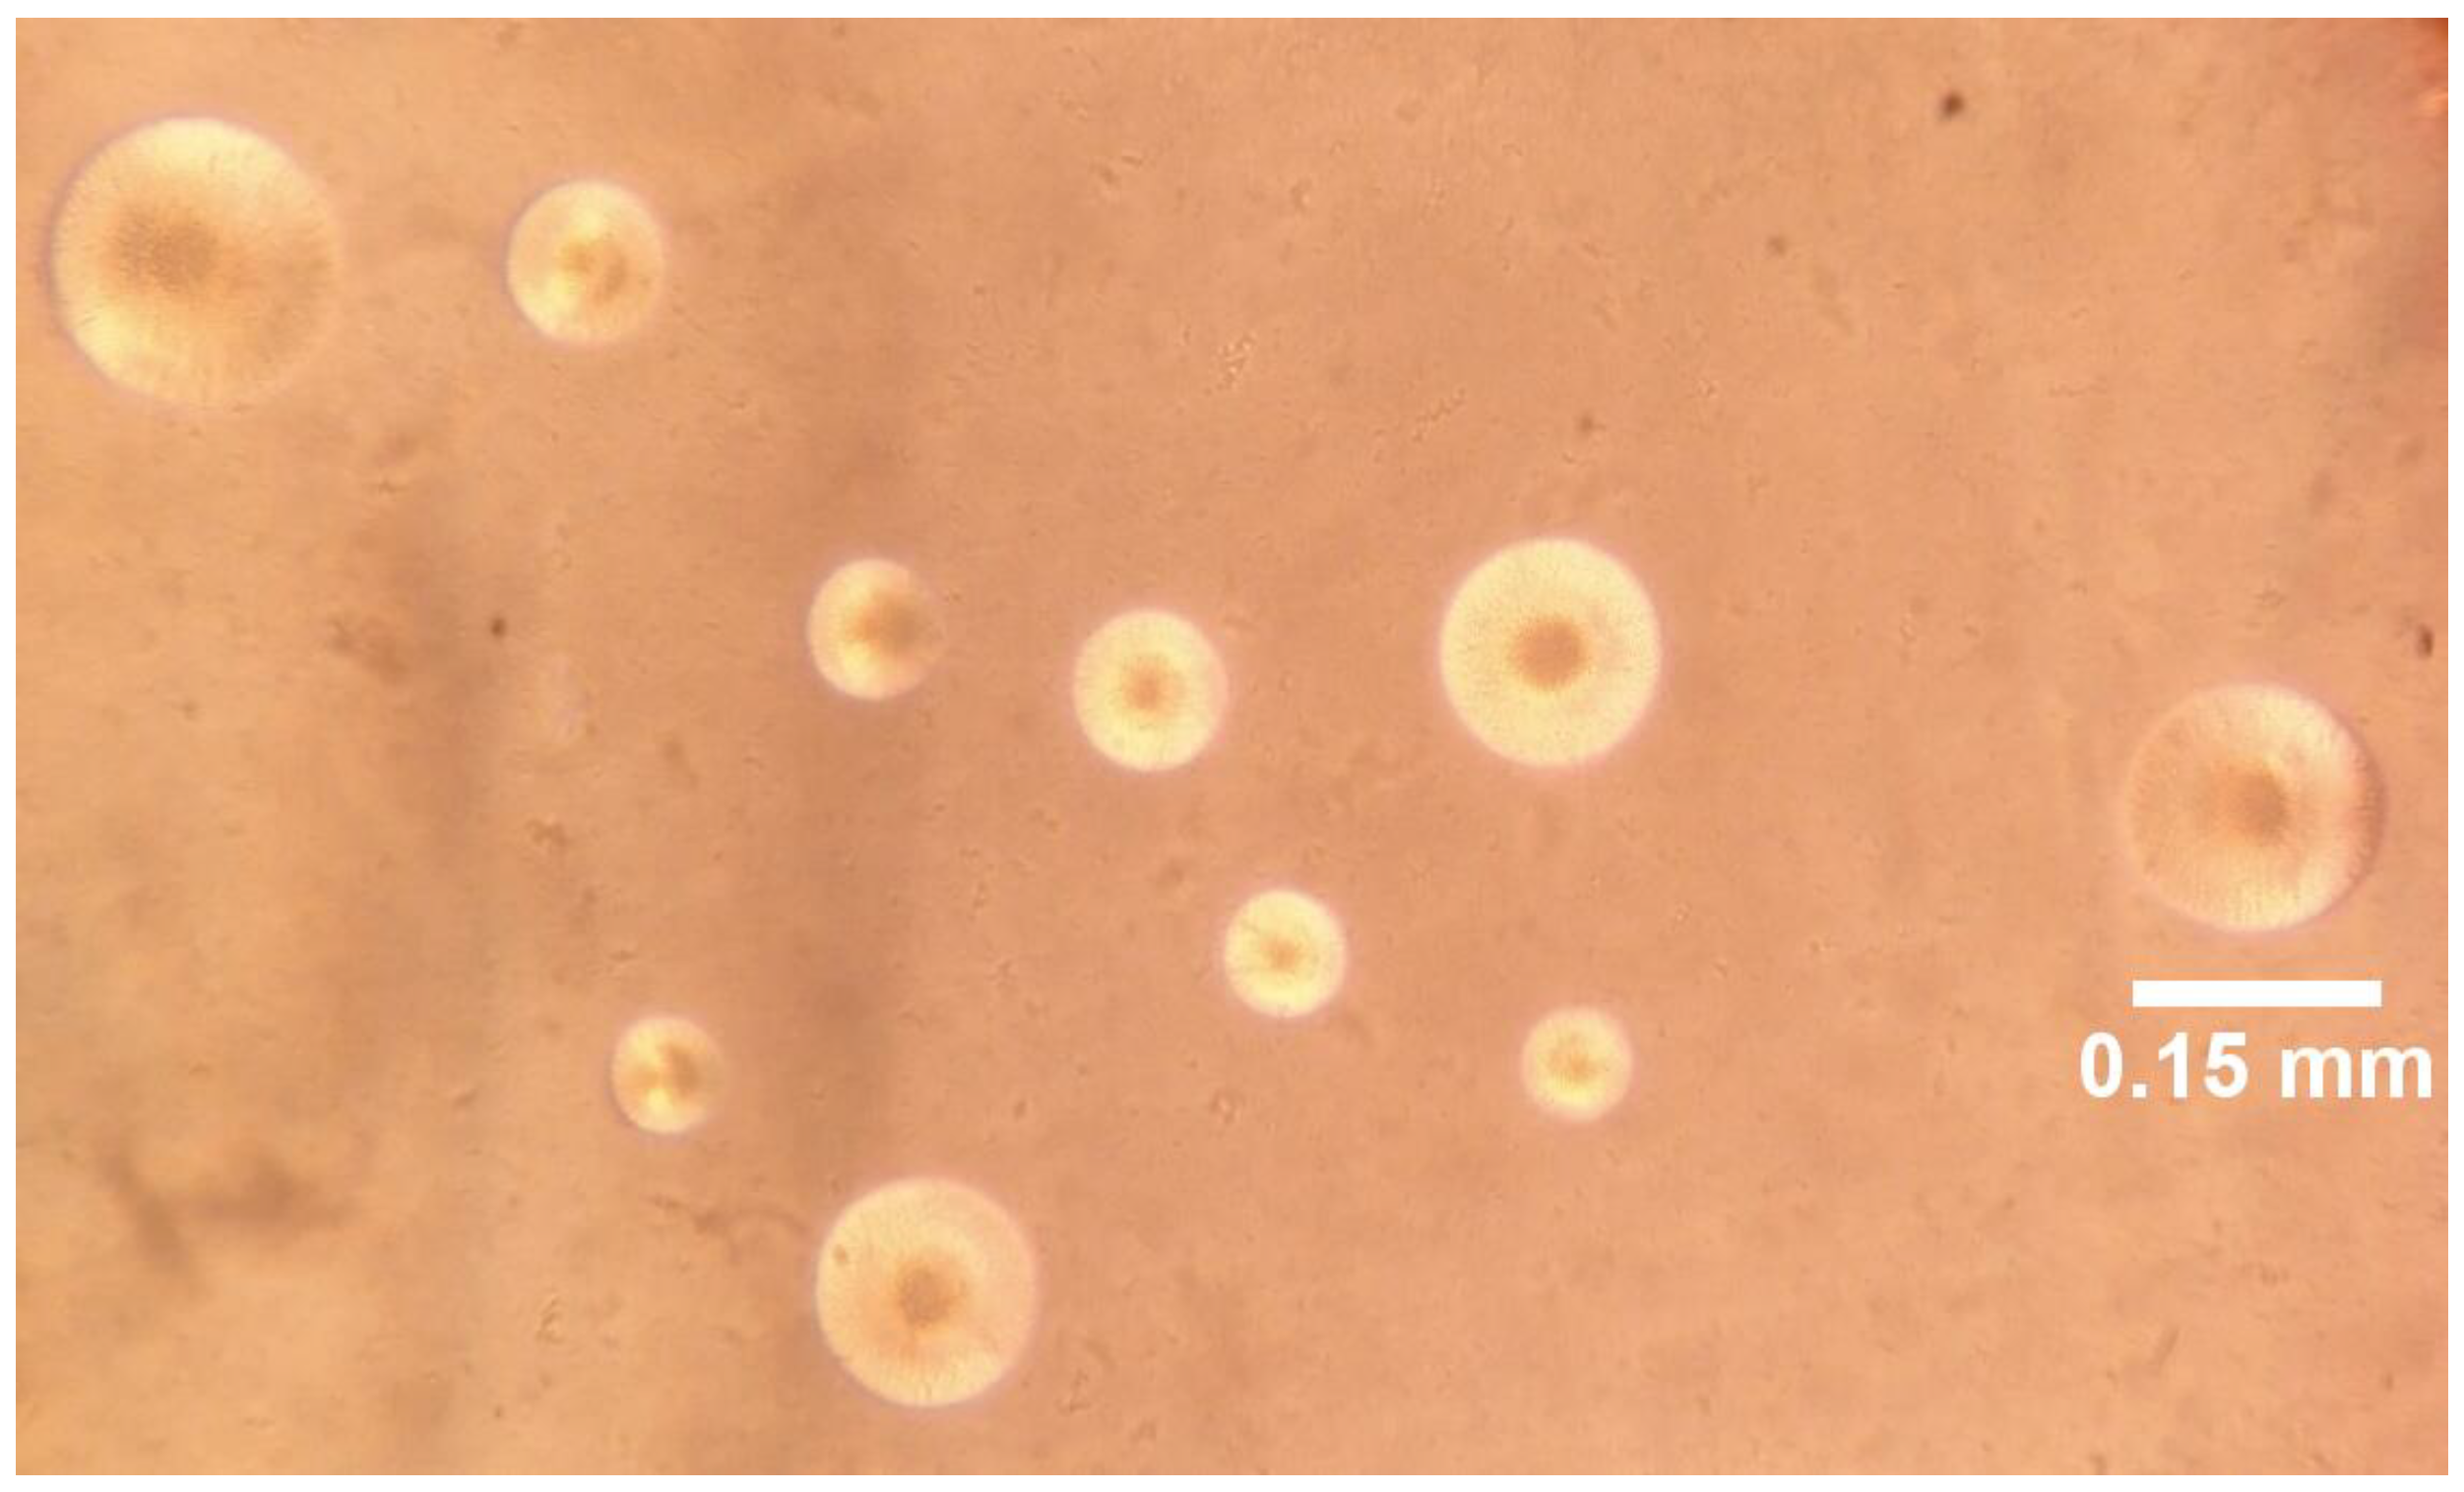

Cultivation of M. pneumoniae

Culture characteristics and biochemical tests